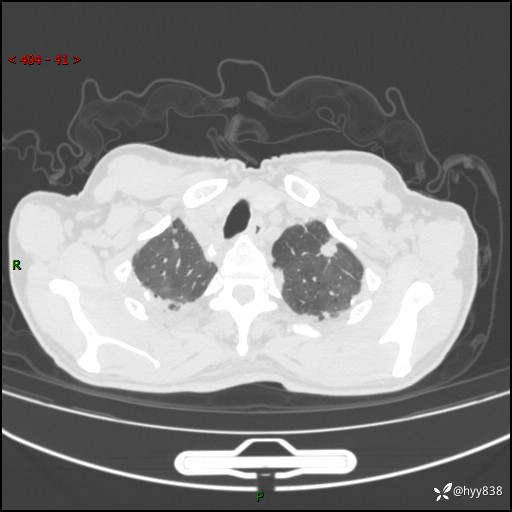

辅助检查:CT

胸部CT平扫